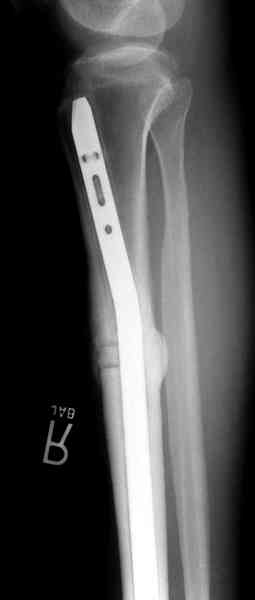

Недавно на нашей ежемесячной Morbidity&Mortality

conference мы разбирали похожий случай, ложный сустав большеберцовой кости после резекции опухоли.

К нашему онкологу-ортопеду обратился больной с жалобами на боли в голени, из рассказа - год назад была сделана биопсия большеберцовой кости, но название заболевания "не запомнил”.

Оперирован в военном госпитале с заменой сегмента

аллокостью большеберцовой кости и после демобилизации явился для постоянного наблюдения по месту жительства.

Наши имели проблему со сращением, пришлось им сделать динамизацию, дополнительную аутопластику.

Снимки представлены.